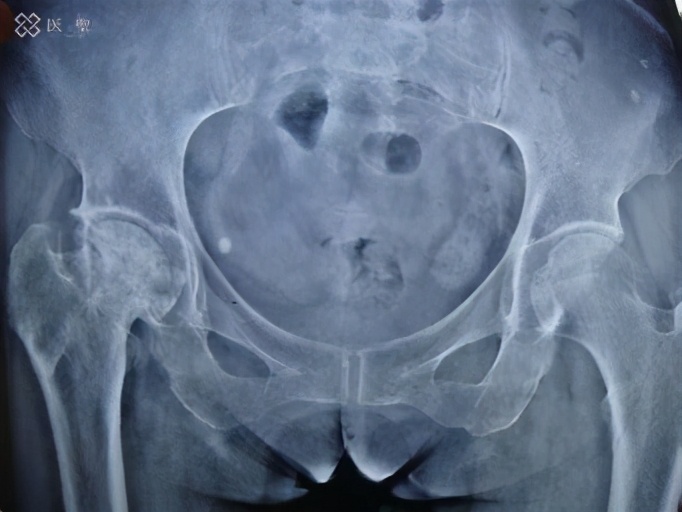

股骨头坏死 ( osteonecrosis of femeral head,ONFH) 是指构成人体最大的球状关节股关节的股骨头的一部分不再通血,骨组织死亡的状态。 发生(发生坏死的状态,也包括无症状性的)和发病(坏死部分溃烂产生疼痛的状态)进行区别处理。

作为胶原病的并发症发生的情况很多。另外,类固醇和酒精摄取等也被认为是发生的危险因素。 另一方面,作为发病的危险因素,坏死的骨头在需要体重的部分中所占的比例越大,越容易被压碎。 如果股骨头坏死发病,就会随着股骨头破裂,自觉髋关节疼痛。 众所周知,从实际坏死到症状出现之间存在时间差,有时也有几个月到几年的时滞。其中流向脚底的骨头(称为股骨头)的血液减少,导致骨头的一部分死亡(坏死)并破裂。

股骨头坏死的发病年龄主要集中在30 ~ 60岁,并且有年轻化的趋势。ONFH 因其早期临床症状不典型, 时常发生漏诊误诊, 大多数患者因此错过最佳治疗时机, 最终导致股骨头 变性 、关节疼痛、活动受限, 其高危害性给患者带来巨大的痛苦。